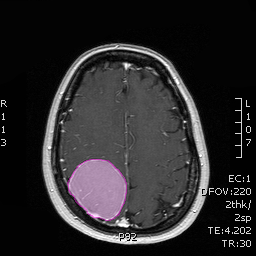

Συμπτώματα Τα συμπτώματα των μηνιγγιωμάτων ορίζονται από τον συνδυασμό της θέσης και του μεγέθους τους. Μικρά μηνιγγιώματα σε επαφή και με πίεση επί ευγενών περιοχών του εγκεφάλου, όπως αυτές που ελέγχουν την κίνηση, τον λόγο ή την όραση μπορεί να προκαλέσουν περισσότερα συμπτώματα από πολύ μεγαλύτερα σε μέγεθος μηνιγγιώματα που πιέζουν λιγότερο σημαντικές περιοχές. Τα συχνότερα συμπτώματα είναι οι επιληπτικές κρίσεις, η αδυναμία ή/και η υπαισθησία (μούδιασμα) σε ένα ή περισσότερα άκρα και οι διαταραχές του λόγου και της όρασης. Όπως προαναφέρθηκε τα μηνιγγιώματα μπορεί να ανακαλυφθούν τυχαία σε απεικονιστικό έλεγχο του εγκεφάλου για διαφορετικούς λόγους, χωρίς να έχουν προκαλέσει (ακόμη) κανένα σύμπτωμα |

Διάγνωση Απαραίτητα είναι: Η λεπτομερής λήψη ιστορικού και η κλινική εξέταση, Η μαγνητική τομογραφία του εγκεφάλου με σκιαγραφικό, Σε ορισμένες περιπτώσεις: Η μαγνητική αγγειογραφία ή/και φλεβογραφία του εγκεφάλου, Η μαγνητική τομογραφία του εγκεφάλου με σκιαγραφικό για νευροπλοήγηση, Ηλεκτροεγκεφαλογράφημα και άλλες εξειδικευμένες εξετάσεις όπως μέτρηση οπτικής οξύτητας και οπτικών πεδίων προτείνονται κατά περίπτωση. |